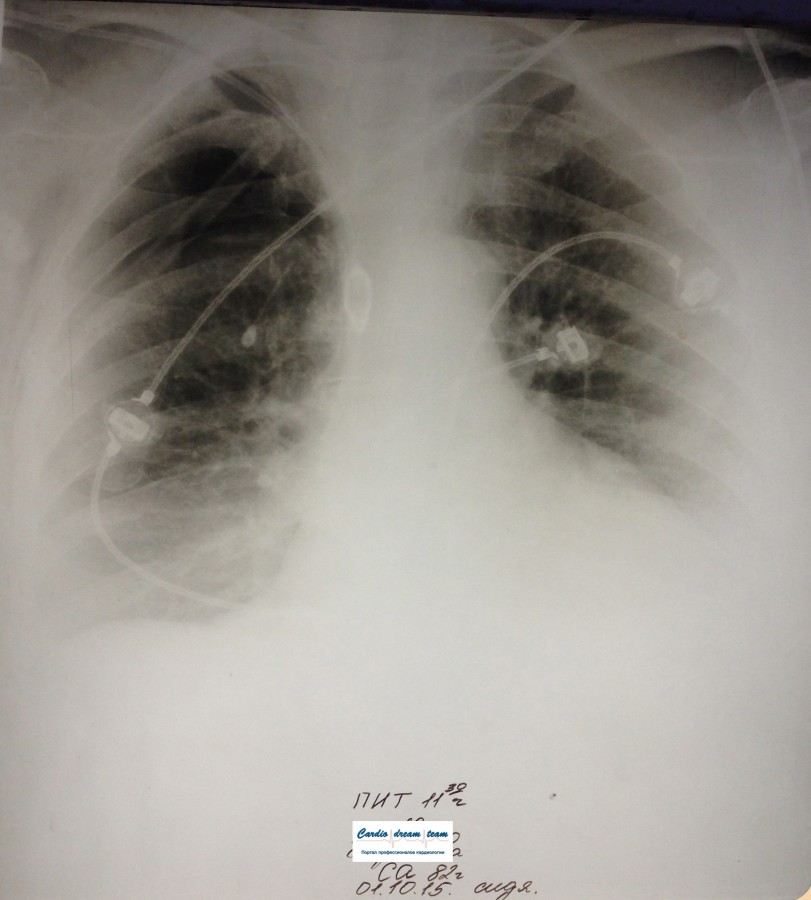

ИССЛЕДОВАНИЕ ОРГАНОВ ГРУДНОЙ КЛЕТКИ Дата 01-ОКТ-15 время 11.30 ОПИСАНИЕ: Проведена рентгенография органов грудной клетки в прямой проекции, положение сидя, условия ПИТ, Р-контроль Легочные поля: Справа легкое расправлено не полностью, апикально до 3го ребра прослеживается свободный газ в плевральной полости. Тень дренажа справа. Тень подключичного катетера в проекции ВПВ. Легочный рисунок: сгущен справа в прикорневой зоне, диффузно деформирован Корни: малоструктурны, обогащены Синусы: нечеткие Сердце: широко лежит на диафрагме (позиционно) ЗАКЛЮЧЕНИЕ: Течение правостороннего пневмоторакса, положительная Р-динамика. Состояние дренирования правой плевральной полости. Р-признаки полнокровия сосудов МКК. Пневмосклероз. Р-контроль .────────────────────────────────────────────────────────────────────── ИССЛЕДОВАНИЕ ОРГАНОВ ГРУДНОЙ КЛЕТКИ Дата 02-ОКТ-15 время 1015 ОПИСАНИЕ: